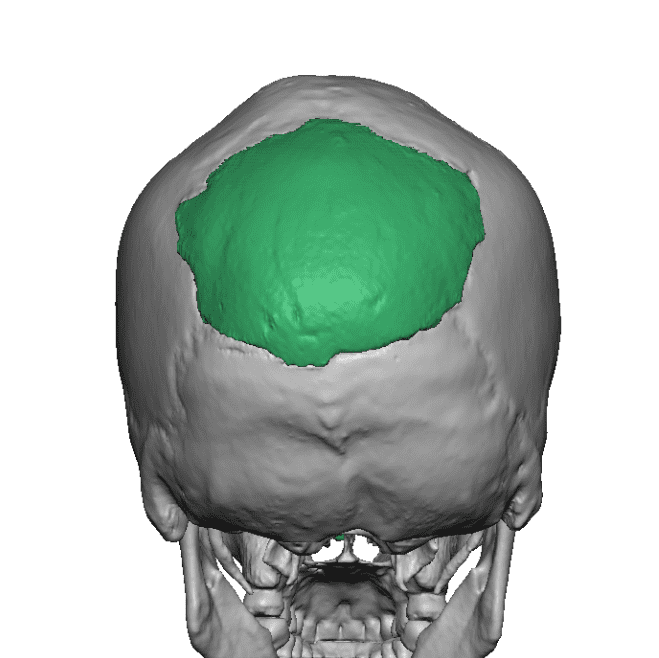

Desire for change of head shape from front view form an inverted V shape to a rounder and wider head shape.

Placement of custom extended forehead-temporal implants through incisions in the crease behind the ear. (he had a prior back of head skull implant which is green in the implant designs and which the head widening implants partially covered it)

Desire for change of head shape from front view form an inverted V shape to a rounder and wider head shape.

Placement of custom extended forehead-temporal implants through incisions in the crease behind the ear. (he had a prior back of head skull implant which is green in the implant designs and which the head widening implants partially covered it)